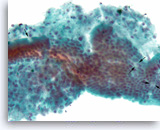

Intraductal papillary mucinous neoplasm #3,

Pancreas FNA, Cell Block.

The tumor cells have high nuclear to cytoplasmic ratio and hyperchromatic nuclei and form papillary architectures. The cigar-shaped nuclei are indicative of the “intestinal type” of IPMN, according to the WHO classification, and there is focal true stratification indicative of high grade dysplasia.

20X

Intraductal papillary mucinous neoplasm #3,

Pancreas FNA, Cell Block.

The tumor cells have high nuclear to cytoplasmic ratio and hyperchromatic nuclei and form papillary architectures. The cigar-shaped nuclei are indicative of the “intestinal type” of IPMN, according to the WHO classification, and there is focal true stratification indicative of high grade dysplasia.

20X